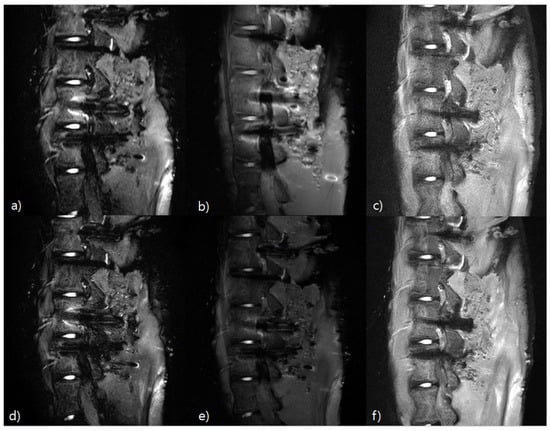

3.3. Histogram Measurement Results

3.4. Qualitative Analysis Results

3.5. Results of Post-Hoc Analysis and Cohen’s Kappa Analysis